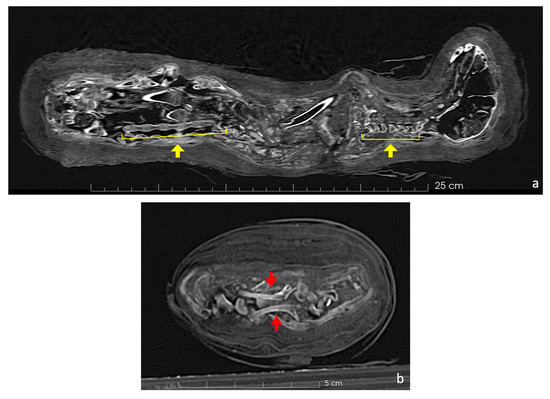

The central part of the body was severely damaged, with all the ribs and several vertebrae displaced from their normal positions. The last cervical vertebra (C7) and the thoracic vertebrae were completely fragmented, while the remaining cervical, lumbar, and caudal vertebrae had experienced less damage and remained in their correct positions (Figure 7a). The first ribs were visible and showed minimal fracturing, even though they appeared rotated by 180 degrees (Figure 7b), contrarily to the other ribs, which were extensively damaged.

Figure 7.

In the coronal view (a), the skeleton shows the cervical and lumbar vertebrae correctly positioned (highlighted by yellow arrows). However, the thoracic vertebrae are severely dislocated and fragmented. In the axial CT scan (b), attention is drawn to two first ribs that are rotated 180 degrees from their normal position (highlighted by red arrows).